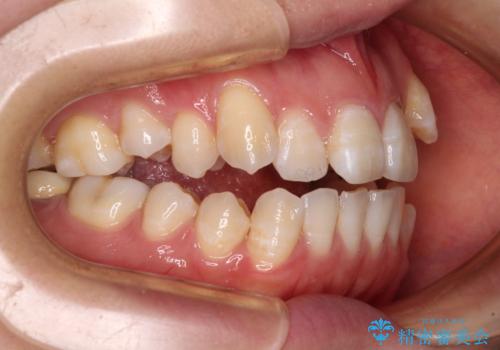

八重歯と開咬の抜歯矯正 ワイヤー装置を併用したインビザライン矯正治療

- 咬み合わない前歯と八重歯などのデコボコを気にして来院された患者様です。

上下前歯の位置を比較すると上顎が前方にあり、デコボコ改善でより上顎が前方に行く可能性があります。

開咬の改善にはインビザラインが有効であり、インビザライン単体での治療を検討しましたが、上顎前突を回避するために上顎左側第一小臼歯抜歯を行うこととしたため、補助装置とワイヤー矯正を併用した上で、インビザラインによる矯正治療を行うこととしました。